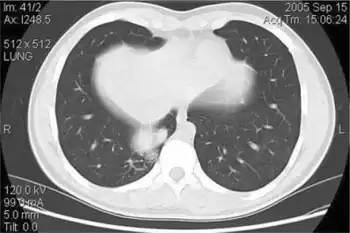

Bochdalek hernia- posterior right costophrenic poorly marginated lesion.